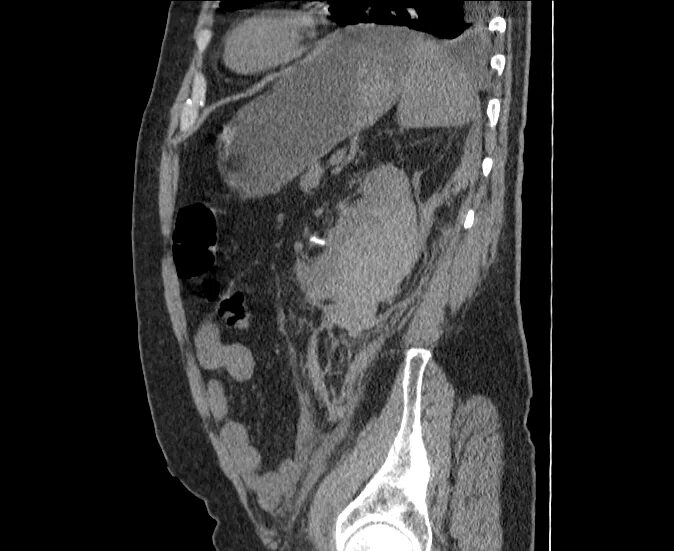

Кальциноз брюшного отдела